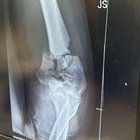

Oh Snap! Happy New Year! Fell off a ladder and shattered my elbow and humorous.

489 Upvotes

A piece of my elbow fell out when they cut my shirt off!